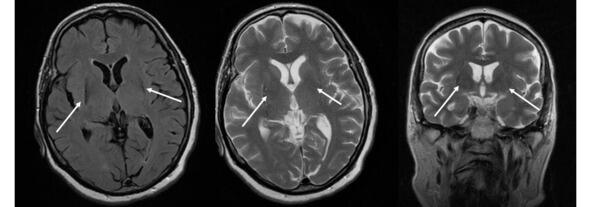

Несмотря на то что МРТ в стандартных режимах не выявляет каких-либо патогномоничных признаков при БП, этот метод позволяет исключить другие структурные поражения мозга, сопровождающиеся синдромом паркинсонизма. К таким патологиям относятся опухоль базальных ганглиев, нормотензивная гидроцефалия, сосудистые поражения, изменения сигнала от базальных ганглиев вследствие болезни Вильсона-Коновалова, отравления марганцем и др. МРТ помогает также в дифференциальной диагностике БП с паркинсонизмом вследствие нейродегенеративных заболеваний, при каждом из которых МРТ имеет ряд специфических симптомов: «глаза тигра» (рис. 14).

Рис. 14. Пример МР-томограмм пациентки 69 лет с «нейродегенерацией с отложением железа в мозге» (NBIA-Syndrom  Neurodegeneration with Brain Iron Accumulation). В проекции базальных ганглиев (отмечены стрелками) выявляются симметричные вытянутые зоны изменения МР-сигнала, неоднородного гипоинтенсивного МР-сигнала на Т2ВИ, Flair, изоинтенсивные на Т1 ВИ, что может соответствовать накоплению железа в базальных ганглиях.